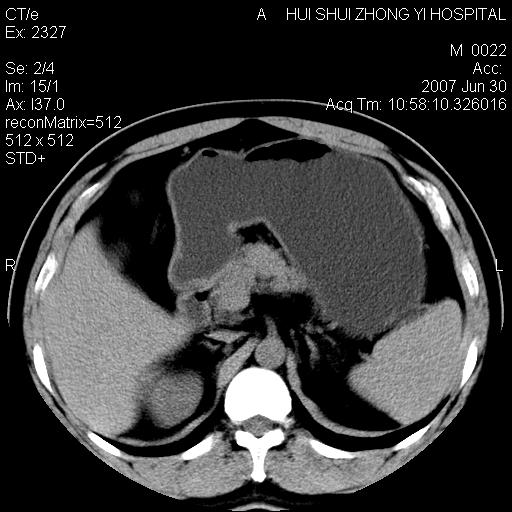

肝右叶密度减低区?

支持双肾结石,肝右叶低密度影为胆囊部分容积效应。

肝右叶低密度影为胆囊部分容积效应?为什么s43.0层面下来不见胆囊影,而是相隔了一层才见胆囊影。这是按我们扫描的顺序发的,但是是追加扫描的。

支持双肾结石,肝右叶低密度影为胆囊部分容积效应

病人呼吸动了,第四层应该在第五\\六层之间。肝右叶低密度影为胆囊部分容积效应。双肾结石。

双肾结石,肝右叶低密度影为胆囊部分容积效应。

考虑:1、水平肝;